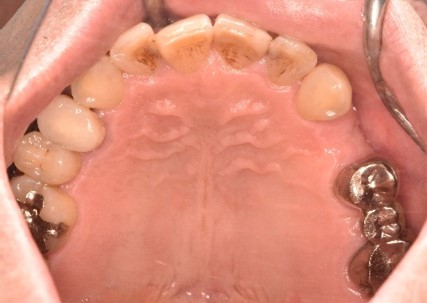

Before

After